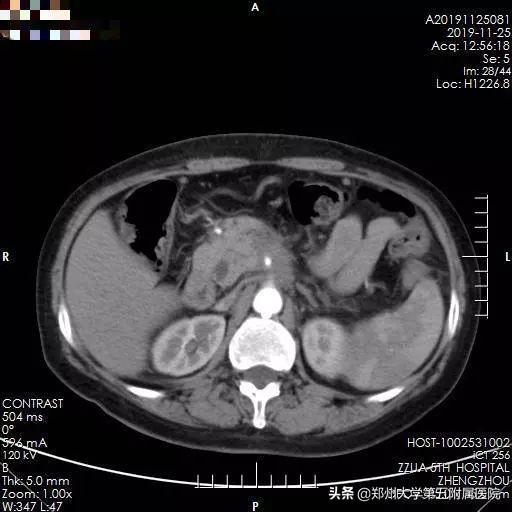

▲ 图 1 患者术前增强CT检查

2019年11月29日下午3点,手术如期进行,在手术室胡强夫主任团队,超声诊断科杨青主任团队缜密的配合下,李晓勇主任团队联合台湾大学附属医院黄凯文教授,通过术前增强CT与术中实时彩超融合引导,精确定位肿瘤位置,精准穿刺布针,纳米刀消融时间约15分钟,术中彩超提示肿瘤消融彻底,效果满意,且周围重要血管流动通畅,未见出血、胃肠道的损伤。